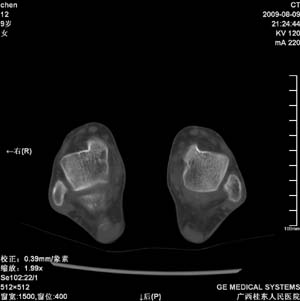

标题: PED2867:右侧内踝肿胀,骨质改变,请各位老师会诊 [打印本页]

标题: PED2867:右侧内踝肿胀,骨质改变,请各位老师会诊

九岁小朋友,近期左侧内踝疼痛,局部肿胀,平时无特殊,近期经常溜干冰

对不起,是右侧内踝肿胀

双踝关节骨质及发育未见异常。